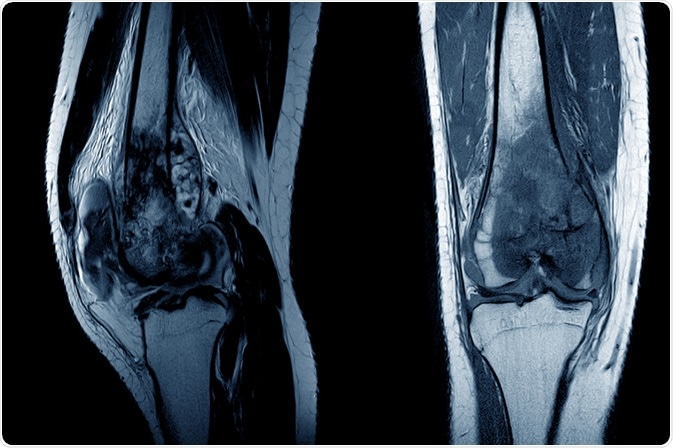

MRI of a knee joint showing osteosarcoma. Image Credit: April stock / Shutterstock.com

MRI of a knee joint showing osteosarcoma. Image Credit: April stock / Shutterstock.com